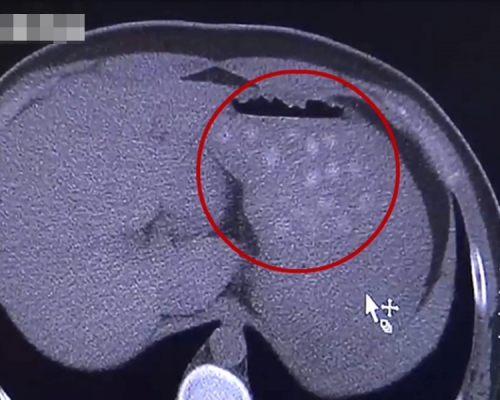

內地媒體報道,大連大學附屬中山醫院近日接獲一宗病例,急診科主治醫生龐洪剛表示,該男生的腹部CT結果讓人大吃一驚,他的胃部擴張腫大、膽囊亦明顯增大,膽壁增厚,而且胃內還有大量圓形小白點,所以診斷為急性膽囊炎。

男生表示,當天吃下很多零食,包括2杯珍珠奶茶,因此醫生確定其胃部的白色小圓點為珍珠,幸好他及時就醫,現已緩解症狀,並無大礙。